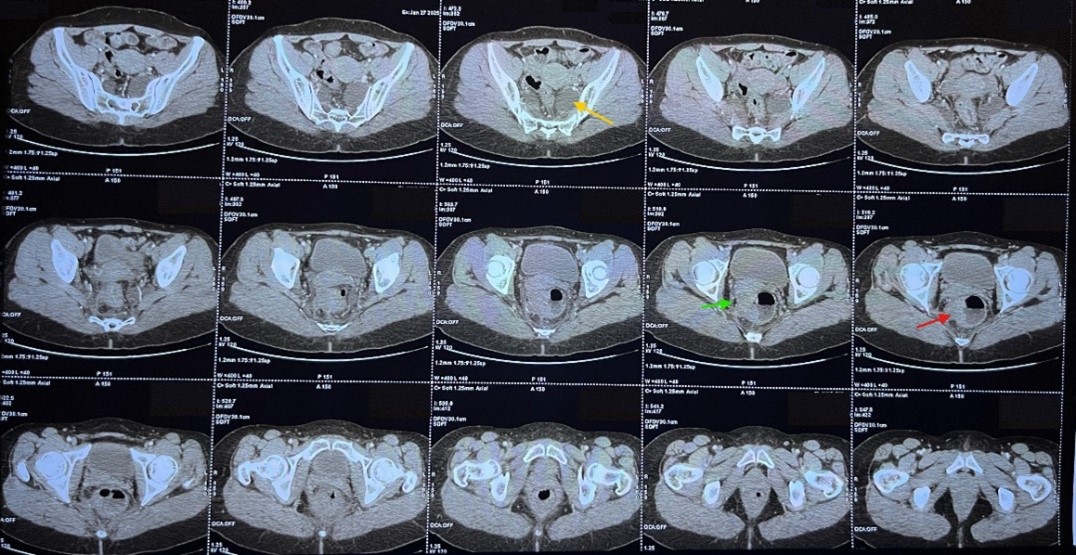

The follow-up thoraco-abdominal CT scan showed no secondary lesions, but the presence of two presacral formations, more prominent on the left, appearing to follow the S1 and S2 nerve roots at the sacral foramina, possibly corresponding to Tarlov cysts.

Figure 3: CT scan image demonstrating the Tarlov cysts (yellow arrow), the tumoral processus (red arrow) and the contact between the tumor and the uterus (green arrow).